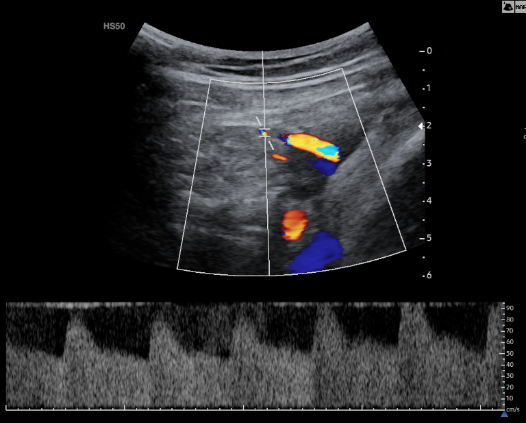

Εικόνα 01 και Εικόνα 02: Φυσιολογική καμπύλη Doppler δεξιάς και αριστερής Μητριαίας Αρτηρίας